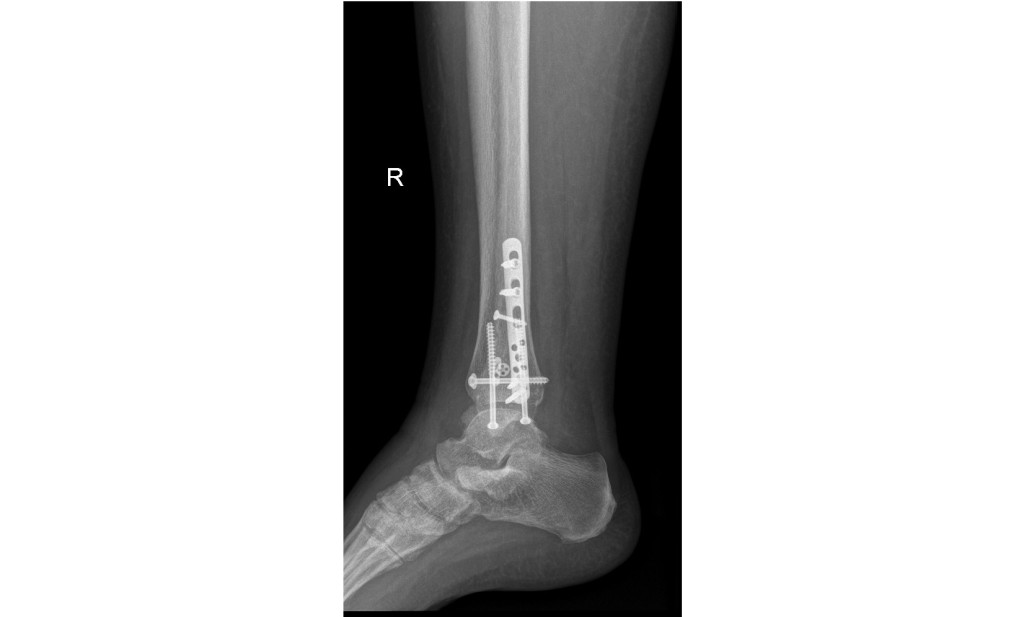

She has 9 screws, a self tensioning fixator and a 6" metal plate in her ankle.

Here's what my wife's ankle looks like: